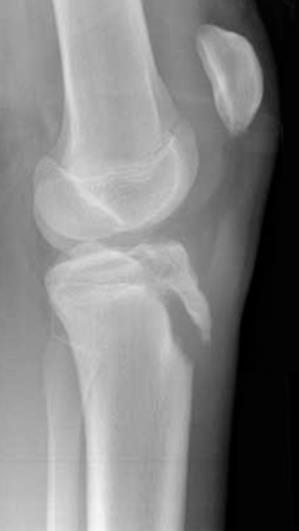

Przedstawiony poniżej obraz Rtg stawu kolanowego wykonany u chorego z bardzo silnym bólem stwierdzanym cztery godziny po urazie, doznanym podczas gry w siatkówkę, upoważnia do:

Pytanie 56